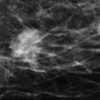

Ung thư vú

» Thông tin: Nữ giới – 72 tuổi.

» Lâm sàng: Khối tuyến vú.